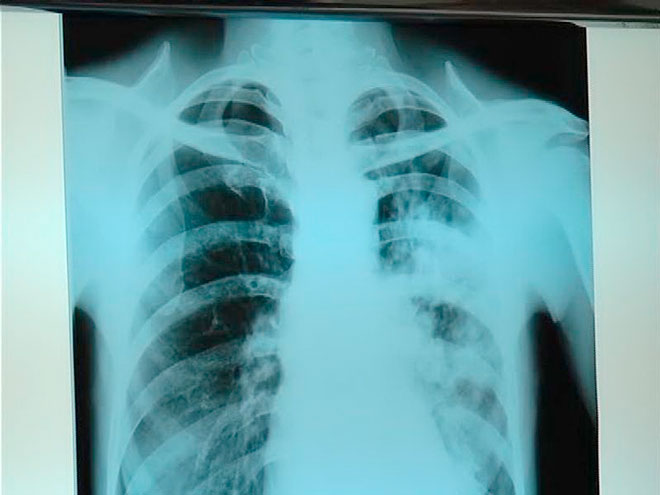

Slučaj babice iz Novog Pazara koja se uspešno leči od tuberkuloze na kragujevačkoj Klinici za pulmologiju, otvorio je pitanje koliko je ova hronična zarazna bolest zastupljena u ovom delu Srbije.

Slučaj babice iz Novog Pazara, koja je na lečenju u kragujevačkoj Klinici za pulmologiju samo je potvrdio statistiku poslednjih godina da je sve više novoobolelih iz redova mlađe ženske populacije.

Prošle godine na Klinici za pulmologiju Kliničkog centra primljeno je 24-oro pacijenata zbog tuberkuloze, dok je samo ove godine već 16 novooblelih, od toga troje iz Novog Pazara.

Tubrkuloza je zarazna bolest, a prenosi se kapljičnim putem i često ima nespecifične simptome, koje se povezuju sa drugim oboljenjima pluća.